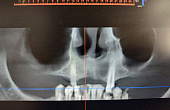

Основной профиль стоматологической клиники «Аладен» – имплантация.

Пациентам предлагают широкий выбор разнообразных линеек имплантов: от базовых израильских до швейцарских премиум-класса.

Высококвалифицированные специалисты с большим опытом работы берутся за самые сложные случаи. В клинике «Аладен» можно вернуть зубы при полной адентии за неделю.